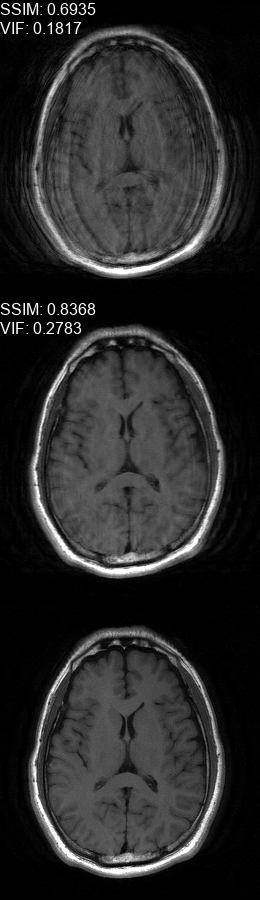

Fig. 5 contains four scan reconstructions from two patient cases. In both cases, the patient was requested to move at a certain time. In order to provide a ground truth for this scenario, another scan was performed using the same protocol for each patient, where the patient was required to hold still. The motion timing information for this case was obtained using the method described in [2] as it requires no additional hardware or changes to the scan protocol. We compare the reconstruction error using the SSIM [17] and the Visual Information Fidelity (VIF) [16] metrics, since a pixelwise comparison is not viable in this case.

Refer to caption

(a)

(b)

(c)

(d)

Figure 5: Examples of real motion corrupted images together with their motion corrected counterparts. The bottom row shows a corresponding slice from a motion-free acquisition of the same subject. These motion-free images were acquired using an additional scan. The images on the top row are motion-corrupted. Images on the middle row were corrected using our method. (a,b) motion was was detected at t1=96subscript𝑡196t_{1}\!=\!96, (c,d) the motion was detected at t1=112subscript𝑡1112t_{1}\!=\!112. All scans were acquired using 𝒮260subscript𝒮260\mathcal{FS}_{260} presented in Fig. 1b.